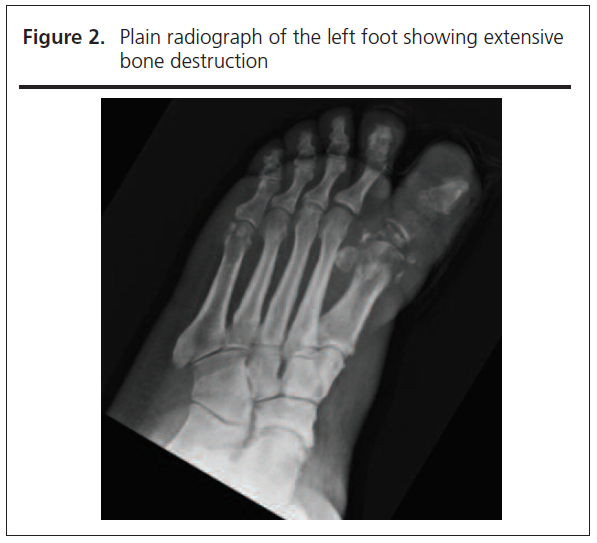

Spinal examination did not reveal any localised tenderness and neurological examination was unremarkable. Blood results on admission showed markedly raised inflammatory markers with a white cell count of 14.9x109/L (neutrophils 12.1x109/L) and a C-reactive protein of 267 mg/L. Plain radiograph of the left foot demonstrated extensive bony destruction of the left hallux (Figure 2), and an MRI scan with contrast confirmed bone marrow oedema extending to the first metatarsal and involving distal tendons of the left hallux, all consistent with osteomyelitis. Time-Resolved Imaging of Contrast Kinetics (TRICKS) suggested significant vascular disease with only the anterior tibial artery being seen, feeding into the dorsalis pedis but not forming a complete plantar arch. There was no evidence of bacteraemia on blood cultures; however, tissue culture from the left hallux isolated coagulase negative Staphylococcus, Streptococcus anginosus and Actinetobacter pittii. Given the ongoing back pain and previous history of spinal osteomyelitis, an MRI scan of the spine was performed which showed discitis with epidural and paravertebral abscess at the level of T9/10 (Figure 3).